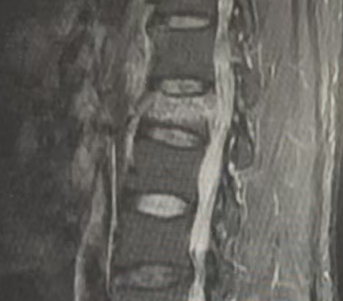

脊柱骨折是一种常见且严重的疾病,尤其是在老年人和骨质疏松患者中更为常见。面对脊柱骨折,许多人会产生一个疑问:“我真的需要手术吗?” 其实,脊柱骨折是否需要手术治疗取决于多种因素,包括骨折的类型、严重程度、患者的健康状况以及其他并发症。今天,我们来为大家全面解答这个问题!

脊柱骨折的治疗方式通常取决于骨折的类型和位置。常见的脊柱骨折类型有:

压缩性骨折:多见于老年人,通常由于骨质疏松引起。压缩性骨折大多数情况下是轻度的,尤其是在没有神经损伤的情况下,可以通过保守治疗(如药物、支具、物理治疗等)进行治疗。

椎体爆裂性骨折:这种骨折较为严重,常伴随脊髓损伤。大多数情况下需要手术干预,以恢复脊柱稳定性,避免并发症。

脊柱脱位或移位骨折:此类骨折伴有脊柱的错位或脱位,通常需要手术治疗来恢复脊柱的稳定性,防止脊髓损伤。